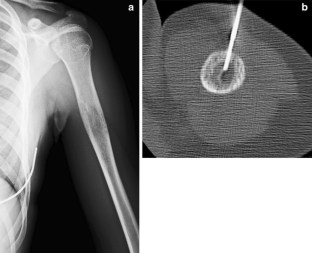

Fig. 1

Fig. 2

Fig. 3

Fig. 4

Fig. 5

Fig. 6

Fig. 7

Fig. 8